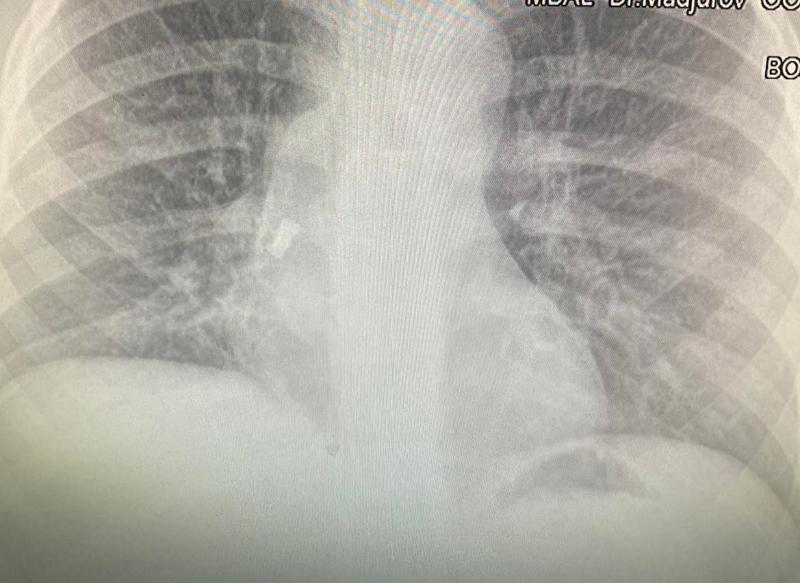

След известно време синът й започва да вдига температура, лекуван е с антибиотици, но температурата продължава. Личният лекар назначава рентгеново изследване и на снимката се вижда зъбът. От него се е развила инфекция на дихателните пътища, което обяснява повишената температура. Момчето е прието по спешност, операцията е извършена почти веднага от УНГ-специалистите доц. д-р Даниел Петков, д-р Ивайло Илиев и анестезиолога д-р Антон Григоров.